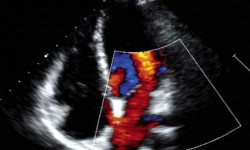

ECOCARDIOGRAMA DOPPLER

Es un examen que emplea ondas sonoras para crear una imagen en movimiento del corazón, y con la que se puede medir y evaluar el flujo de sangre a través de las cavidades y las válvulas del corazón.

- Permite estudiar con detalle todas las estructuras cardiacas (aurículas, ventrículos, válvulas, etc), y detectar si hay alguna anomalía en su morfología o en su funcionamiento.

- Puede detectar un flujo de sangre anormal en el interior del corazón, lo que indicaría problemas, como una abertura entre las cavidades del corazón, el mal funcionamiento de una o más de las cuatro válvulas cardiacas o un deterioro en las paredes del corazón. De este modo se estudia con precisión el tamaño del corazón, su movimiento, o el estado de sus válvulas.

Existen varios tipos de ecocardiograma doppler.

Ecocardiograma Doppler transtorácico. Ecocardiograma Doppler transesofágico

Ecocardiograma de estrés con esfuerzo. Ecocardiograma de estrés farmacológico

Ecocardiograma con contraste. Ecocardiograma 3D